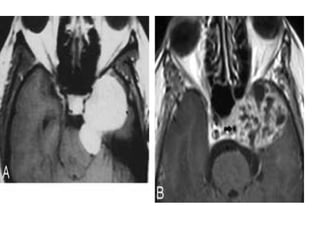

• #45 Cavernous hemangiomas. A, Axial post contrast T1-weighted image shows a large and homogeneously enhancing mass arising from the lateral wall of the left CS. B, Axial post contrast T1-weighted image in a different cavernoma, which shows inhomogeneous contrast enhancement but also arises from the lateral wall of the CS, pushing the ICA (arrow) medially. When a mass arises in the lateral wall of a CS, the most important differential diagnosis is that of meningioma versus cavernoma.

• #46 Hemangioma: hemangioma appears as a very well delineated lesion of the left cavernous sinus (white arrows), hyperintense on T2-wi (a), associated with progressive and centripetal enhancement (black arrow: b, c).

• #48 Nasopharyngeal carcinoma: nasopharyngeal carcinoma invading both cavernous sinuses with carotid encasement and mass effect on the pons. The tumor appears with an intermediate signal on T2-WI (a) and heterogeneous enhancement on T1-wi after contrast (b).